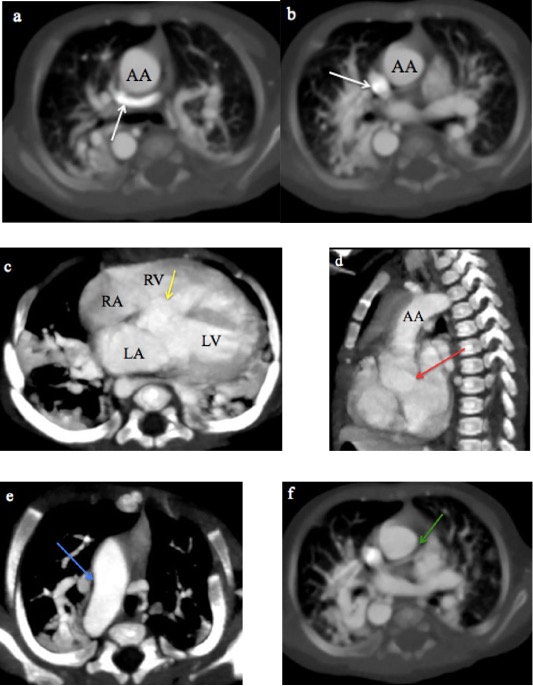

MDCT images of TAPVC are shown in Figures 4 and 5, demonstrating the characteristic drainage patterns of the supracardiac and infracardiac types, respectively.

Fig. 4 A 2-month male infant with supracardiac total anomalous pulmonary venous connection. (a-b) CT Pulmonary angiography axial MIP sequential images from caudal to cranial levels showing the left pulmonary veins (LPV) and right pulmonary veins (RPV) converging to form a vertical vein (VV) that drains into the superior vena cava (SVC). (c-d) Coronal MIP images demonstrating the VV draining into the SVC.

TAPVC, in which all four pulmonary veins drain into the systemic veins rather than the left atrium, is usually diagnosed on echocardiography4. However, MDCT angiography is indispensable when echocardiographic visualization is limited or complex CHD is suspected. The supracardiac type of TAPVC was the most common in this study (45.5%), consistent with previous reports (45%-55%)8,10. In our study, MDCT angiography effectively characterised various drainage patterns, including a supracardiac TAPVC draining into the SVC and a rare infracardiac type of TAPVC draining into the splenic vein, also reported by AI Mutari et al26. MDCT’s 3D reconstructions provided crucial details for accurate delineation of venous stenosis.